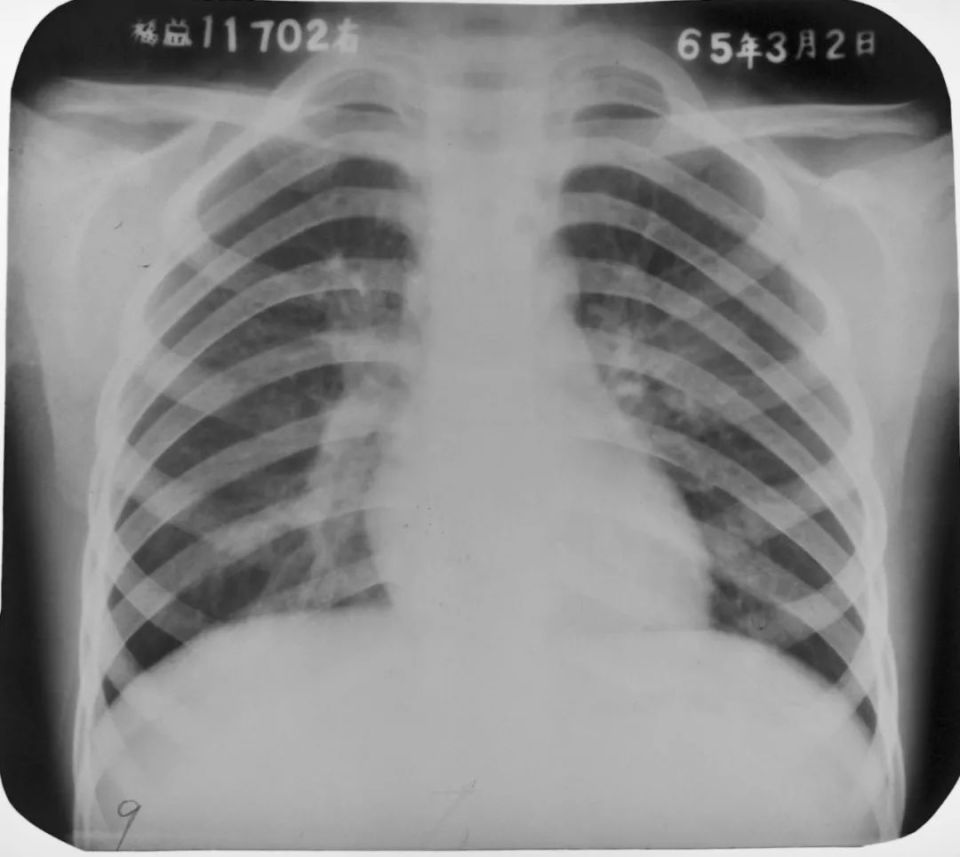

两肺支气管肺炎

图片

胸部正位片示:两肺多发不规则的小片状或斑片状边缘模糊的致密阴影,阴影密度不均,中间密度高,边缘淡,局部融合呈片状分布